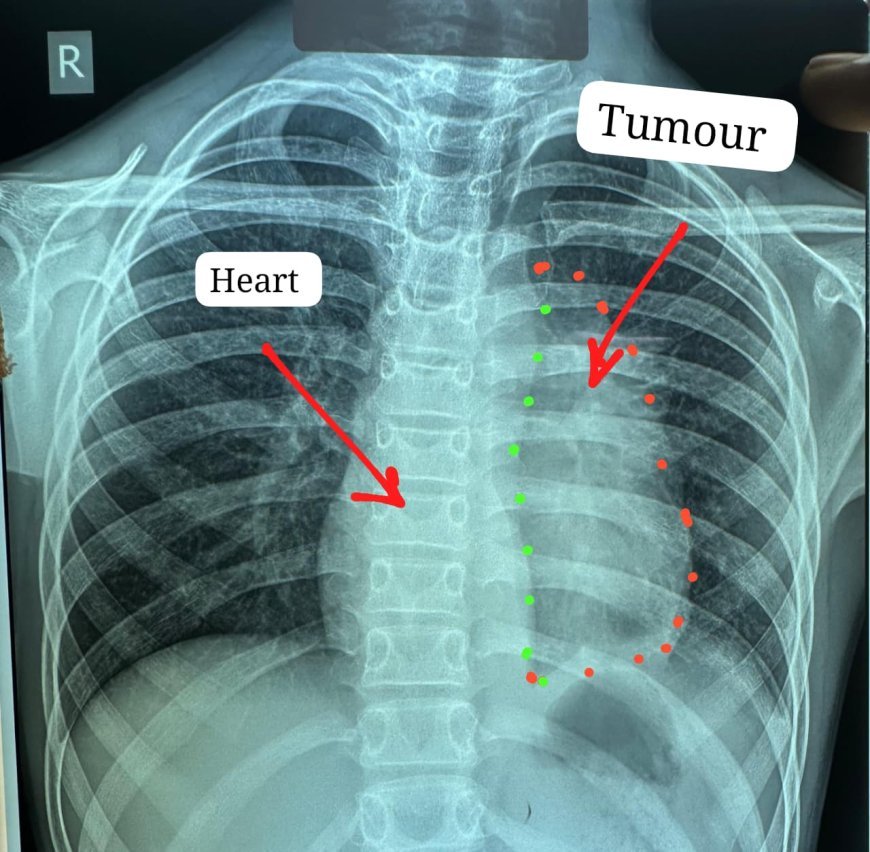

UNITED NEWS OF ASIA. अमृतेश्वर सिंह, रायपुर ।  छत्तीसगढ़ के सबसे बड़े शासकीय अस्पताल डॉ. भीमराव अम्बेडकर स्मृति चिकित्सालय में चिकित्सा क्षेत्र की एक ऐतिहासिक सफलता सामने आई है। अस्पताल के हार्ट, चेस्ट एवं वैस्कुलर सर्जरी विभाग ने 11 वर्षीय बच्चे के दिल से चिपके अत्यंत दुर्लभ और जटिल स्टेज-3 इनवेसिव थायमिक कैंसर (टाइप-बी थायमोमा) को सफलतापूर्वक निकालकर विश्व स्तर पर नया कीर्तिमान स्थापित किया है।

यह जटिल सर्जरी विभागाध्यक्ष डॉ. कृष्णकांत साहू और उनकी टीम ने की। ट्यूमर हृदय के साथ-साथ पेरिकार्डियम, फ्रेनिक नर्व, महाधमनी (एओर्टा), मुख्य पल्मोनरी आर्टरी, लेफ्ट एट्रियम और फेफड़े से चिपका हुआ था। ऐसे मामलों में ट्यूमर को पूरी तरह निकालना लगभग असंभव माना जाता है, लेकिन आधुनिक तकनीक और हार्ट-लंग मशीन की सहायता से यह संभव हो सका।

ट्यूमर का आकार लगभग 12×8 सेंटीमीटर और वजन करीब 400 ग्राम था। इसे निकालने के लिए ड्यूल एप्रोच तकनीक अपनाई गई, जिसमें छाती की हड्डी (स्टर्नम) और पसलियों दोनों ओर से चीरा लगाया गया। इस प्रक्रिया को स्टर्नोटॉमी और थोरेक्टोमी कहा जाता है।